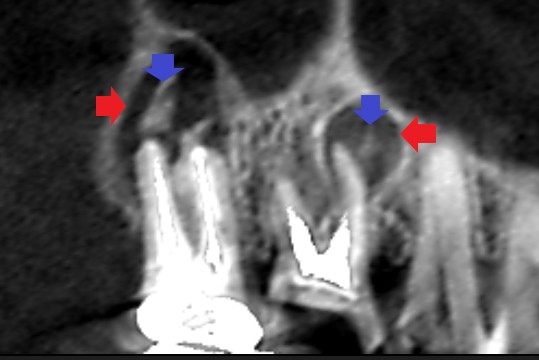

赤い矢印の先に大きな膿の影がみられます。膿の中には白い根管充填材らしい物質(青い矢印の先)の存在が確認されます。根管充填材を足掛かりにして細菌が繁殖している可能性があります。

再根管治療12ヶ月後のCT画像です。第一大臼歯は精密再根管治療のみ、第二大臼歯は精密再根管治療で改善がみられなかったため、歯根尖切除術を行いました。第一大臼歯、第二大臼歯共に膿の影の縮小と歯槽骨の再生がみられます。